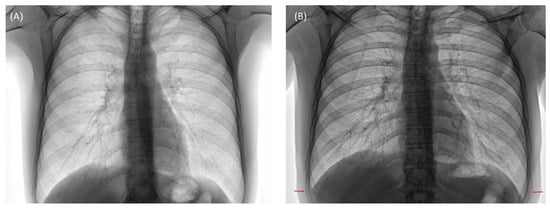

- Daccache, A.; Haddad, J.; Ghanem, A.; Feghali, E.J.; El Osta, B. Cough-Induced Rib Fracture in a Smoker: A Case Report. J. Med. Case Rep. 2020, 14, 147. [Google Scholar] [CrossRef]